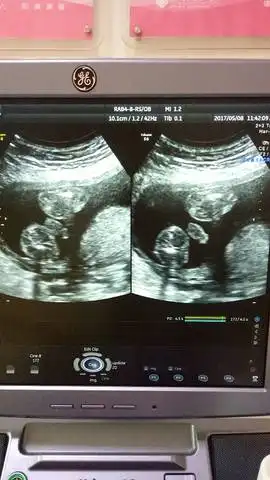

四维彩超看男女这么简单, 学到了

区别图一般来说,怀孕到了四个月的时候,胎儿的生殖器官已经开始发育了